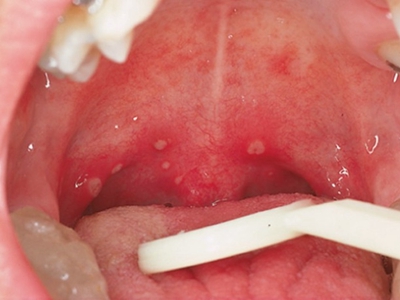

疱疹性咽炎症状图片

疱疹性咽炎潜伏期3-10天,多以突发高热开始,可升至39℃-41℃,伴头痛、咽部不适、肌痛等,婴幼儿常呕吐、拒食,甚至发生高热惊厥;年长儿童常见严重的咽痛、吞咽困难、四肢肌痛、厌食乏力等,持续4-5天后,咽部出现灰白色小丘疹,24小时内发展为水疱和溃疡,其周围绕以直径1-5mm的红晕为特征性的病变,皮损常现于扁桃体前柱、软腭缘和悬雍垂,经1-5天溃疡愈合,一般3天内退热,7日内症状消失。一般疱疹性咽炎往往都伴有牙龈出血、口腔异味,还可伴有颌下淋巴结肿大,但很少波及口腔外部的皮肤。